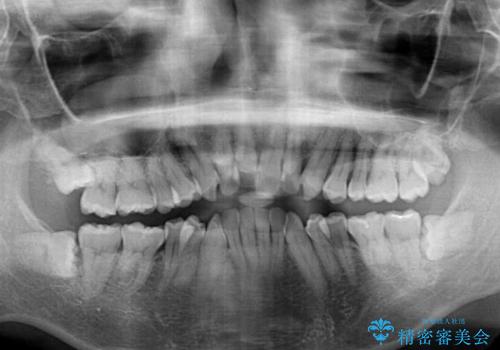

- 口元の閉じにくさと、前歯のでこぼこの歯並びを気にして来院された患者様です。

口元を積極的に引っ込めるために、上下左右の小臼歯計4本を抜歯することとしました。

叢生が強い場合、抜歯スペースが叢生を解消するために消費されるため、口元の突出感があまり改善されないことがあります。

今回の治療では、奥歯が前方に傾斜した歯並びだったため、奥に起き上がることで歯列が後方に移動し、横側からも口元が引っ込んだ感じが分かるほど改善されました。